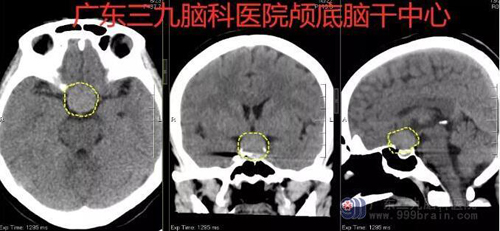

医生通过专科检查,发现其左眼视力1.5米数指,右眼视力4.3,CT示鞍区占位性病变,范围约2.23cm×2.36cm×2.39cm。经过检查,她被确诊为垂体大腺瘤,明确病因后,为古女士制定了“内镜下经鼻蝶垂体瘤切除术”的治疗方案。术程顺利,术后左眼视力4.5,右眼视力5.0。病理报告示: 术后病理示(鞍区)促性腺激素细胞腺瘤。目前古女士正在进一步康复治疗中。

图1:术前CT示鞍区占位性病变,鞍区示一高信号占位性病变,范围约2.23cm×2.36cm×2.39cm